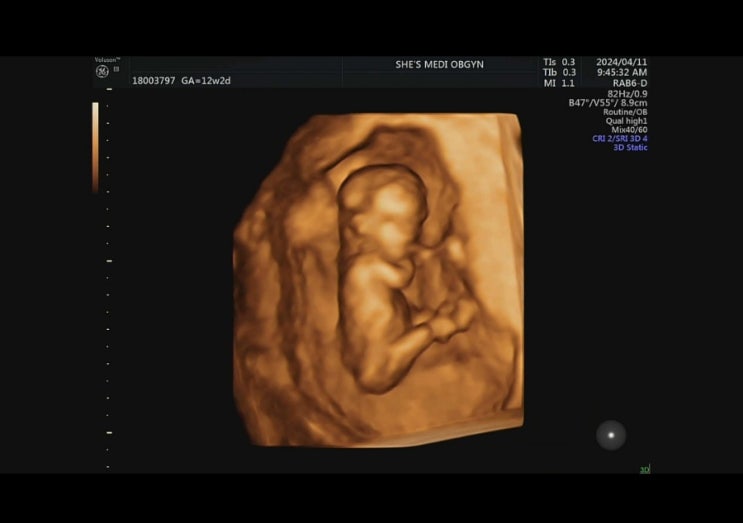

임신 4개월 12-15주차 기록(12주차 1차 기형아 검사)

여전한 입덧... 언제쯤 끝나려나 싶은 입덧이었다. 하루 종일 울렁거리는 속 때문에 뭘 먹을 수도 없고, 못...